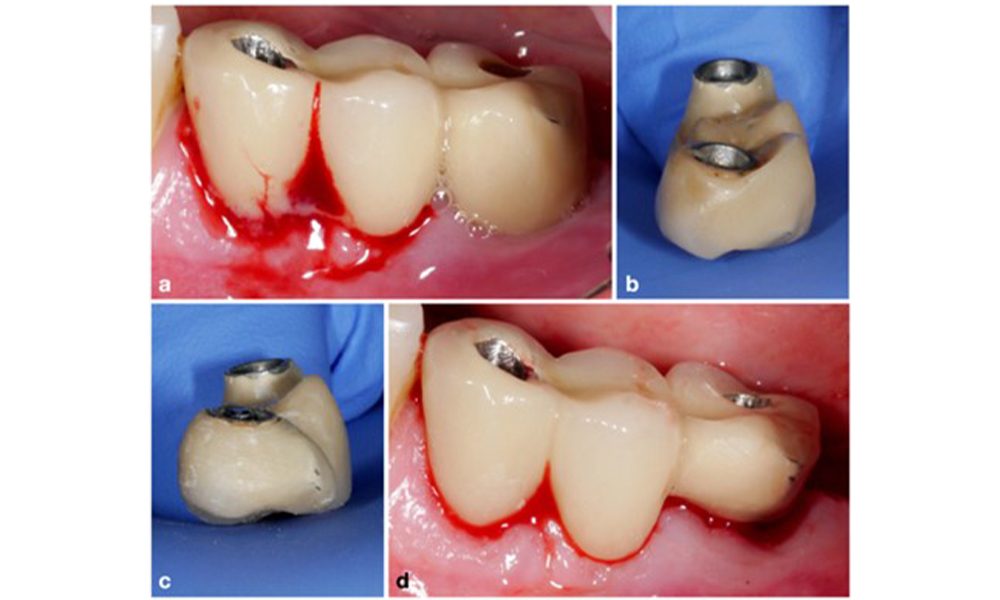

Patient case with peri-implant mucositis, poor oral hygiene and calculus accumulation (a). In such case the combination of different equipment is advisable, i.e., specially designed tips for ultrasonic scalers are necessary to remove the calculus (b), and an air-polishing device helps in removing remaining soft biofilm (c–d).